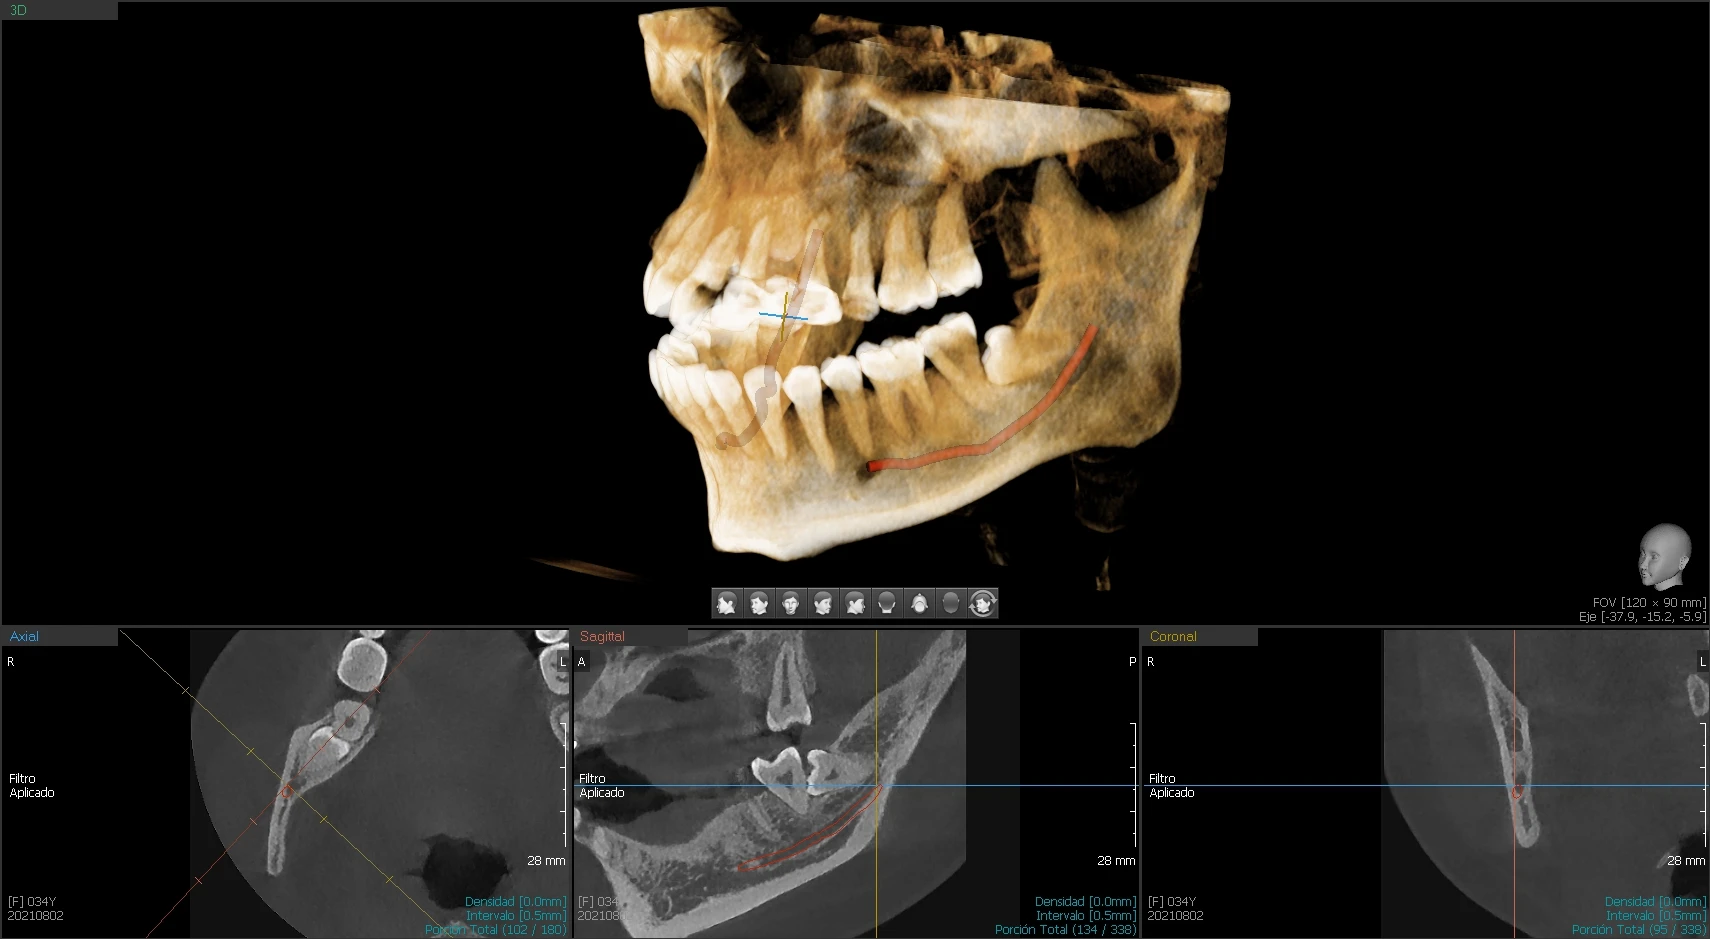

ANWENDUNGEN:

• Radiologie: Ganzkörper-CT.

• Interventionelle Medizin: Biopsie, Ablation, Therapie etc.

• Strahlentherapie: CT-Simulation.

• Onkologie: Tumordarstellung, -beurteilung, -überwachung, Therapiekontrolle etc.

• Orthopädie: 3D- und VR-Bildgebung, Frakturdarstellung.

• Medizinische Untersuchungsstelle: Niedrigdosis-Detektion, automatisierte Diagnostik.

• Neurologie: Schlaganfall-Diagnostik und Gefäßmorphologieanalyse.

• Pneumologie: Analyse von Lungenrundherden, Pneumonie und Lungenfunktionsprüfung.